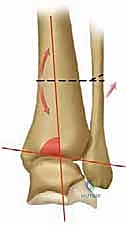

في حالة التشوه التقوسي (Varus Deformity)، يحدث ميلان في المحور الميكانيكي للساق. تخيل أنك تقود سيارة وإطاراتها غير متوازنة (Misaligned). سيؤدي ذلك إلى تآكل جانب واحد من الإطار بسرعة أكبر بكثير من الجانب الآخر. هذا بالضبط ما يحدث في الكاحل التقوسي؛ حيث ينتقل محور تحمل الوزن (Weight-bearing axis) بشكل غير طبيعي نحو الداخل (الجانب الإنسي). هذا التركيز المفرط للإجهاد يفوق قدرة الغضروف على التحمل، مما يؤدي إلى تشققه، تآكله، وفي النهاية تلامس العظم بالعظم، وهو ما يسبب الألم المبرح والالتهاب.

السبب الرئيسي هو وجود ميل تقوسي في السطح المفصلي البعيد لعظم الساق. قد يولد بعض الأشخاص بمحور ميكانيكي يميل قليلاً للتقوس، ومع مرور سنوات من المشي وتحمل الوزن، يتفاقم هذا الميلان مؤدياً إلى الخشونة.

* المنظر الأمامي الخلفي (AP View): لتقييم المسافة المفصلية وتحديد زاوية سطح الساق (Tibial Anterior Surface Angle - TAS).

* منظر سالتزمان (Saltzman View): وهو منظر إشعاعي متخصص جداً لتقييم محاذاة الكعب الخلفي بالنسبة لمحور الساق، وهو أمر حاسم في التخطيط الجراحي.